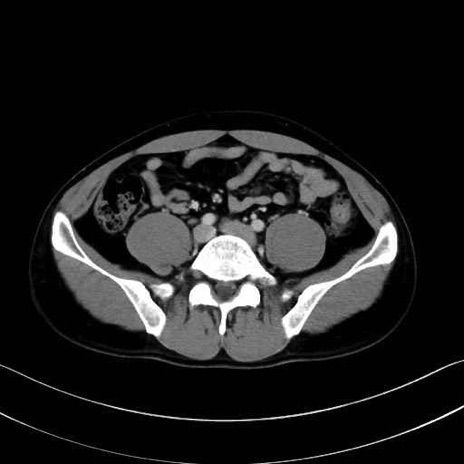

内閉鎖筋 (Obturator internus)

外閉鎖筋 (Obturator externus)